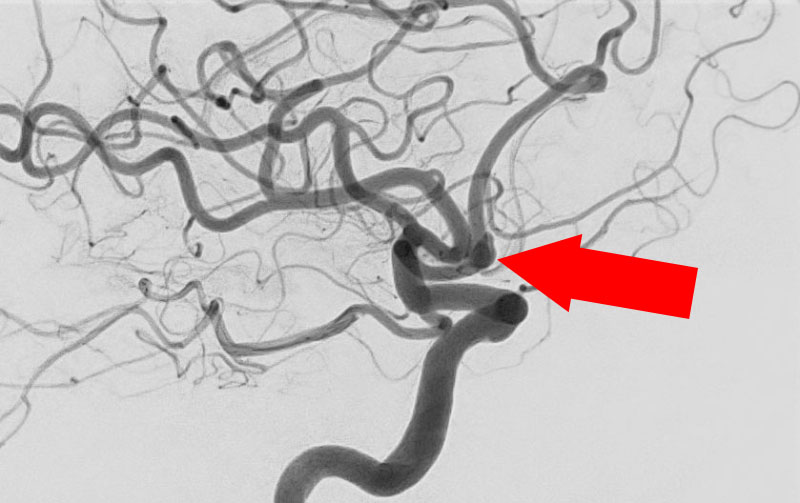

'26年4月

左後下小脳動脈瘤

80代

大阪府の病院